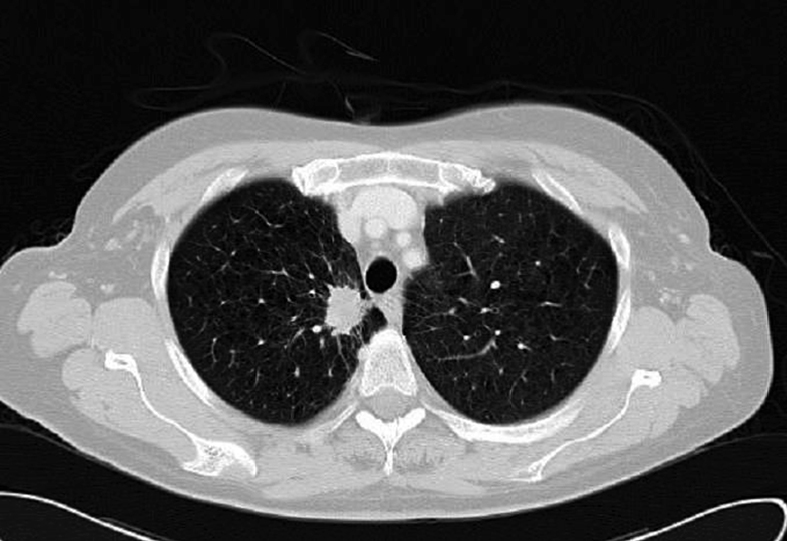

Figura 2. TAC torácico que demuestra nódulo pulmonar espiculado en segmento apical del lóbulo superior derecho con retracción pleural mediastínica adyacente de aspecto neoplásico; correspondiente con el tumor primario.

Se solicitó asimismo un TAC toraco-abdominal donde se detectó un nódulo espiculado en el lóbulo superior izquierdo sugestivo de malignidad (Figura 2) y una lesión focal hepática de aspecto metastásico.